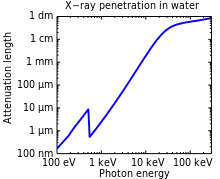

X-rays with high photon energies above 5–10 keV (below 0.2–0.1 nm wavelength) are called hard X-rays, while those with lower energy (and longer wavelength) are called soft X-rays.[71] The intermediate range with photon energies of several keV is often referred to as tender X-rays. Due to their penetrating ability, hard X-rays are widely used to image the inside of objects (e.g. in medical radiography and airport security). The term X-ray is metonymically used to refer to a radiographic image produced using this method, in addition to the method itself. Since the wavelengths of hard X-rays are similar to the size of atoms, they are also useful for determining crystal structures by X-ray crystallography. By contrast, soft X-rays are easily absorbed in air; the attenuation length of 600 eV (~2 nm) X-rays in water is less than 1 micrometer.[72]

Hard X-rays can traverse relatively thick objects without being much absorbed or scattered. For this reason, X-rays are widely used to image the inside of visually opaque objects. The most often seen applications are in medical radiography and airport security scanners, but similar techniques are also important in industry (e.g. industrial radiography and industrial CT scanning) and research (e.g. small animal CT). The penetration depth varies with several orders of magnitude over the X-ray spectrum. This allows the photon energy to be adjusted for the application so as to give sufficient transmission through the object and at the same time provide good contrast in the image.